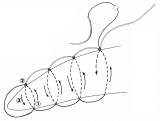

胃全摘術後の再建

器械吻合器を用いた、ρ‐double tract法。